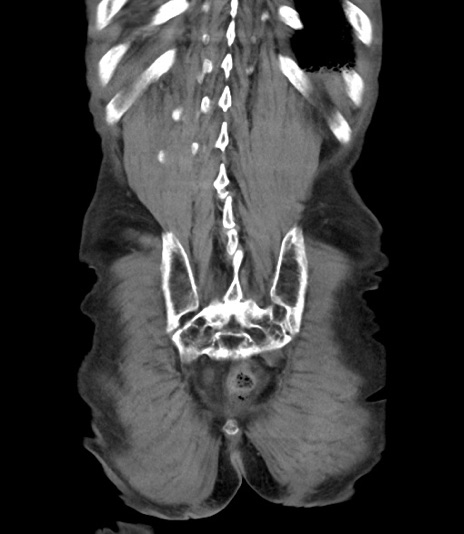

症例3(冠状断像)